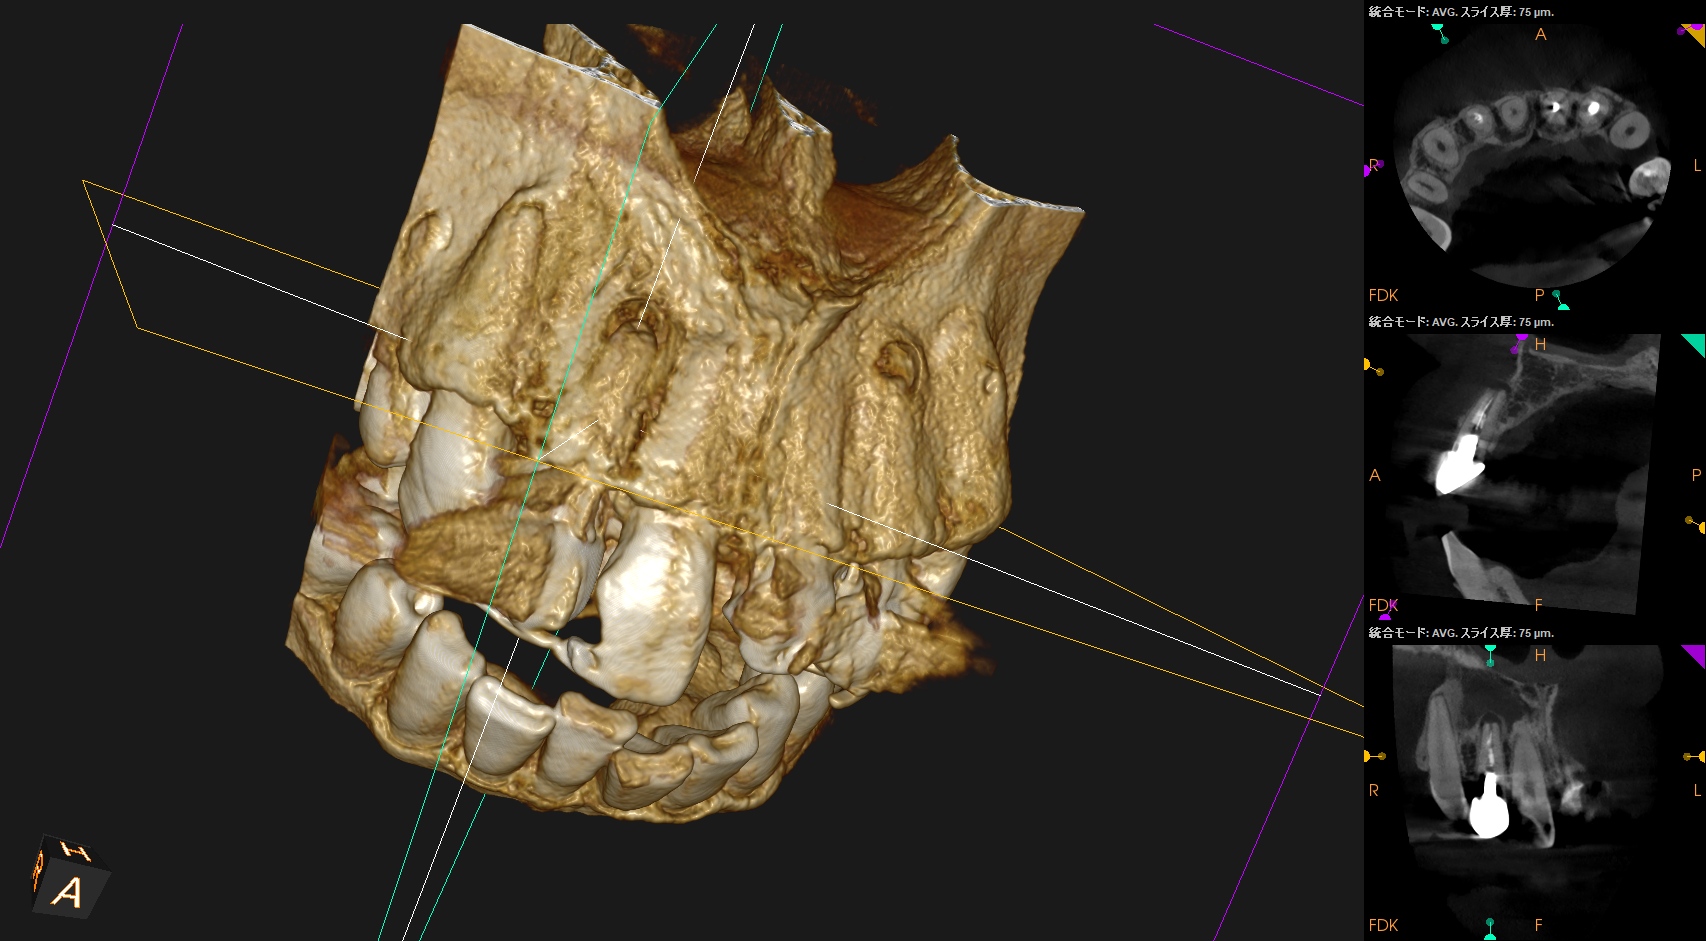

CBCT(2025.1.16)

#7

頬側皮質骨が消失している。

これが圧痛の原因だろう。

#10

#10も#7に同じである。

根管形成・当該部位への根管充填がほぼなされていないように見えることから, 再根管治療へ移行した。